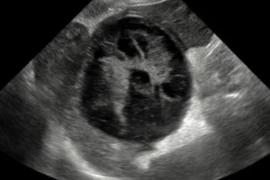

Ultrasound Modular Course April 2025

Referent: Catheryn Walsh

Dr Catheryn has worked in general practice for 12 years. She received a membership in diagnostic imaging in 2018, has a special interest in internal medicine, and a graduate certificate in abdominal ultrasound. She is currently undertaking post graduate study in cardiology. She runs her own mobile ultrasound business and analyses radiographs for other vets on a regular basis.